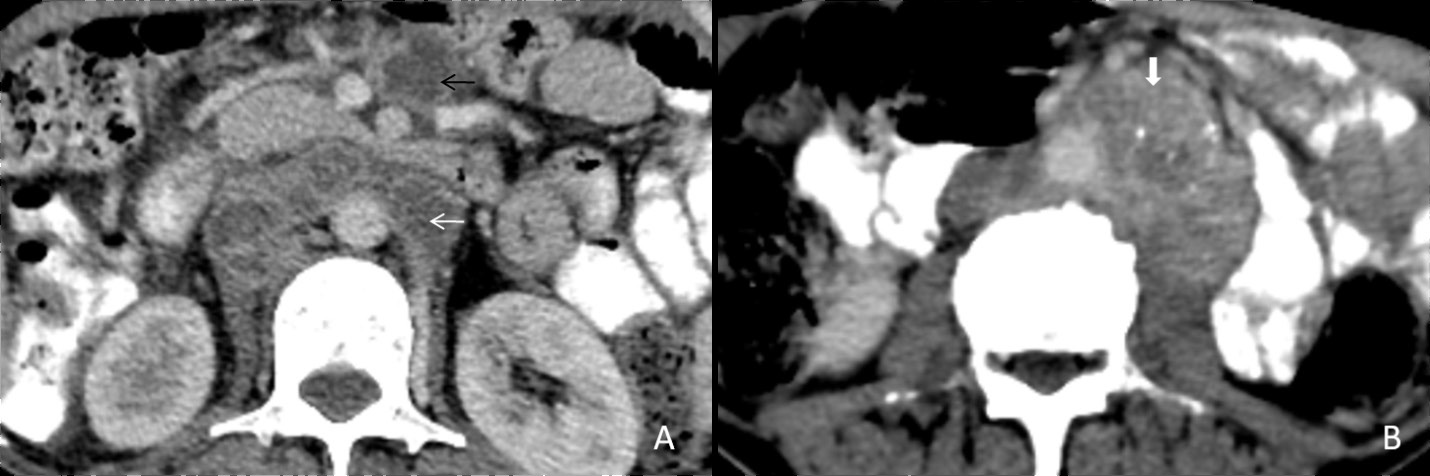

Tubercular lymphadenitis

Lymphadenopathy is the commonest finding associated with abdominal tuberculosis. A wide range of patterns can be seen, including an increase in the number of lymph nodes to large nodal masses. The commonly involved lymph nodes groups are omental, mesenteric, celiac, portahepatis and peripancreatic. The conglomerated pattern of lymph nodes is commonly seen in abdominal tuberculosis. In contrast, CT features of involved lymph nodes may vary from peripherally enhancing lymph nodes with low-density centres (signifies caseous necrosis) to homogeneous/heterogeneous enhancement. Lymph nodes calcification is also seen in chronic tubercular infection (Figure 1A,1B). The necrotic lymph nodes are not pathognomic for tuberculosis as they can also be seen in metastasis, lymphoma or Whipple’s disease [4].

Figure 1: (A) A 30 years old male patient came with a complaint of vague pain abdomen, low-grade fever and a history of significant weight loss in the recent past. On physical examination, there was diffuse pain in the abdomen without any organomegaly. Postcontrast computed tomography image from a venous phase in the axial plane illustrates multiple, conglomerated, peripherally enhancing para-aortic (white arrow) & mesenteric (black arrow) lymph nodes with central necrosis. (B) In another 60 years old male patient with similar complaints, a post-contrast computed tomography image from a venous phase in the axial plane shows heterogeneously enhancing, enlarged, and conglomerated lymph node masses with internal low attenuating areas and punctate calcification (thick white arrow) in the left para-aortic region. Both these patients were diagnosed with TB on CT guided lymph node FNAC and anti-tubercular therapy was started. Patients are now symptomatically better and kept on follow up.